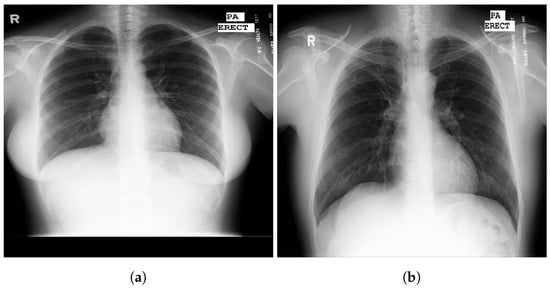

3.1. COVID-19 Image Data Collection (CIDC)

3.2. COVID-19 Radiography